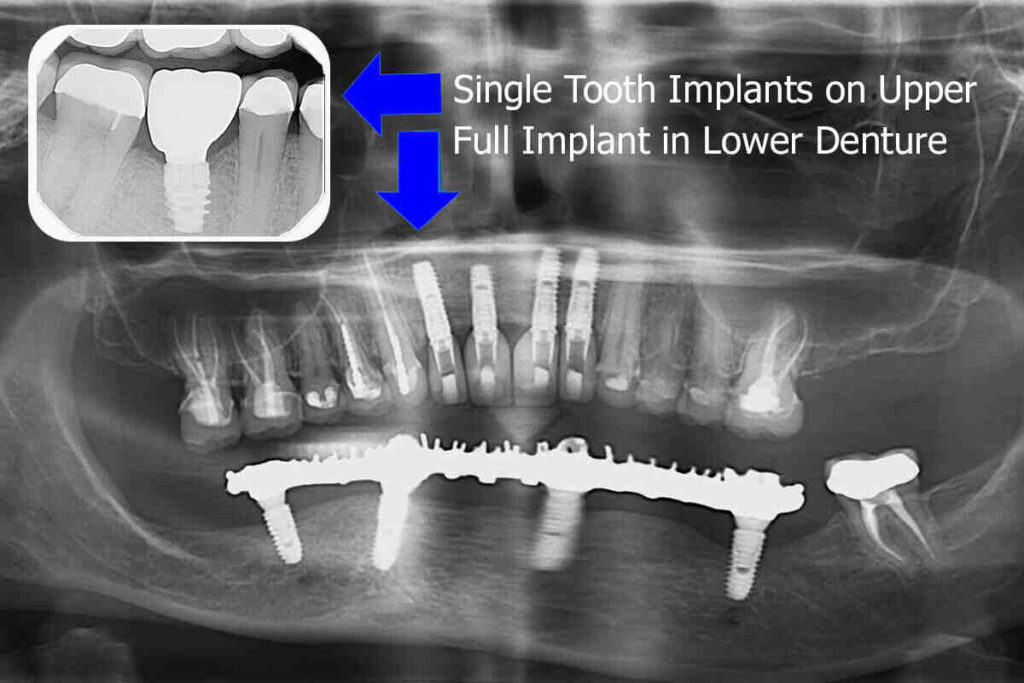

Guided Implants How It's Done Phoenix Dental Implants Blog